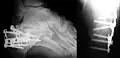

Radio d'une fracture du calcanéus.

Radio d'une fracture comminutive du calcanéum